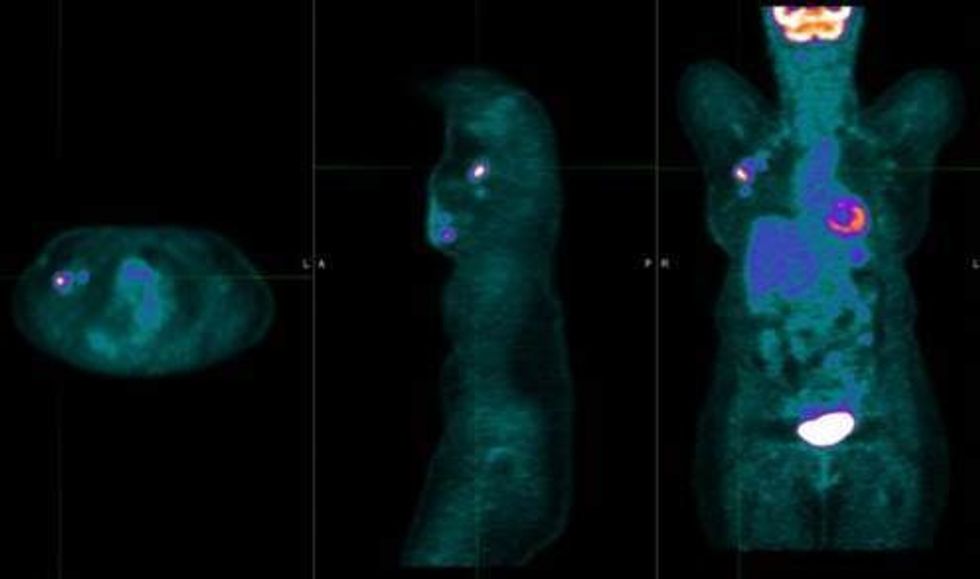

Që nyja sentinel të lokalizohet me saktësi, pranë tumorit injektohet marker radioaktiv, ngjyrë speciale ose kombinim i të dyjave. Këto substanca ndjekin rrjedhën natyrale të limfës dhe “shënojnë” nyjen e parë ku ajo mbërrin.

Kirurgu më pas, me ndihmën e sondës ose vizualisht, e identifikon atë nyje dhe e heq përmes një prerjeje të vogël. Procedura kryhet më së shpeshti njëkohësisht me operacionin për largimin e tumorit, por mund të bëhet edhe veçmas, varësisht nga situata klinike.